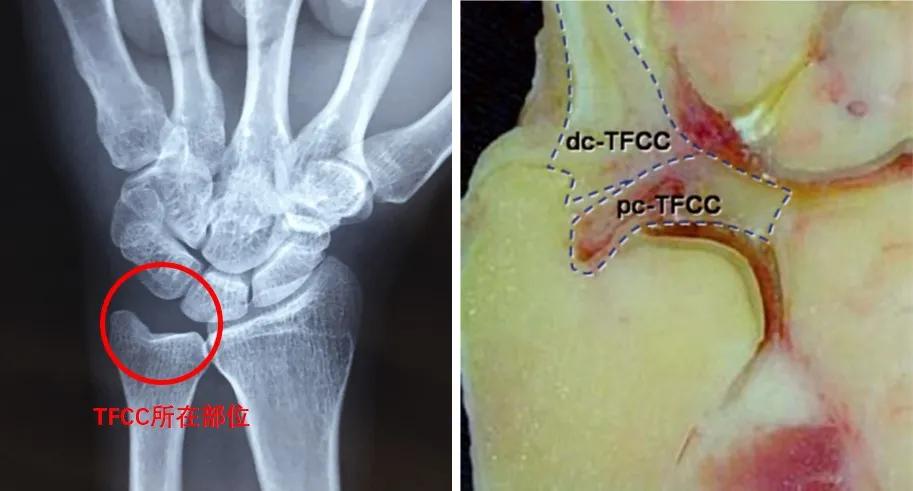

三角纤维软骨复合体是位于腕关节尺侧,连接桡骨远端、尺骨远端及腕骨,由纤维软骨及韧带组成的复合结构(图1)。TFCC的主要作用是稳定下尺桡关节及尺腕关节,缓冲腕关节尺侧的负荷,并且参与腕关节的运动[1,2]。

图1 TFCC所在位置及组成(右图来源于参考文献2)